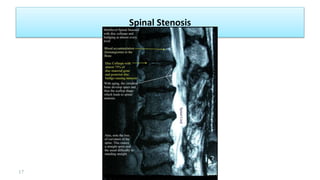

Spinal Stenosis

• Spinal stenosis: Narrowing of the vertebral canal by bone or soft tissue elements.